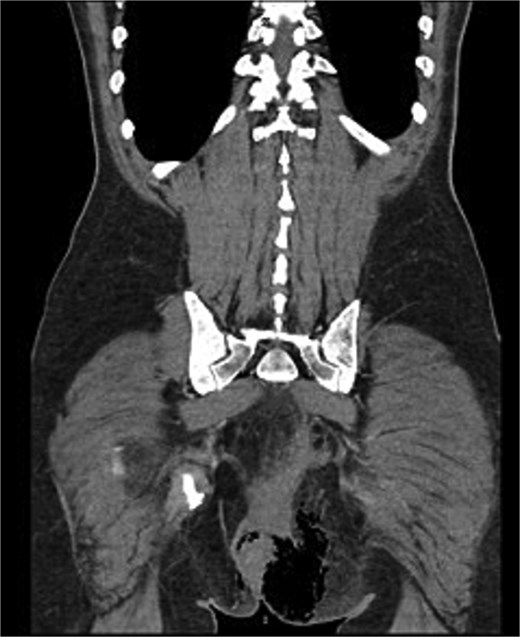

Histopathological analysis revealed a moderately differentiated adenocarcinoma. Colonoscopy showed no additional lesions and tumour markers were normal. PET-CT excluded distant disease. Pelvic MRI demonstrated involvement of the left levator ani, mesorectal fascia, and suspicious lymph nodes, suggestive of cT4bN1a disease (Fig. 4).